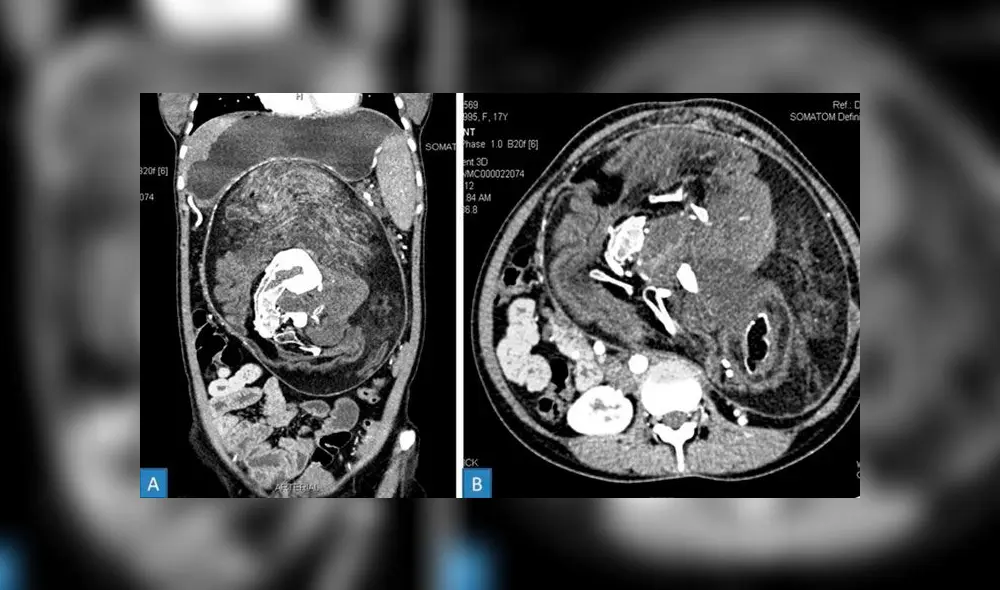

“Una masa bien definida” fue identificada en el abdomen de la joven gracias a una tomografía computarizada con contraste. En las imágenes se pudo observar que dicha masa contaba con elementos de tejido adiposo y secciones con formas semejantes a huesos (vértebras, costillas, etc.).

La masa había involucrado toda el área abdominal de la joven. Imagen: BMJ Case Reports.